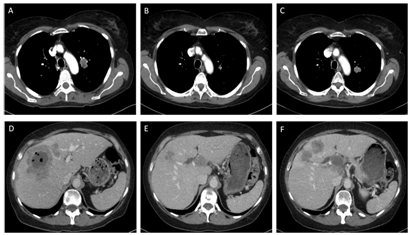

A treatment with erlotinib 150 mg/day was started in July 2014 and imaging in September 2014 showed partial response (Figure 1). In October 2014 a new metastasis in the liver was detected, which was treated with stereotactic radiotherapy in November 2014. Since the other lesions were stable, treatment with erlotinib was continued until there was progression of the primary tumor and liver metastases in February 2015 (Figure 1).

Figure 1 A-C Computed tomography images of the thorax of patient #2 showing an adenocarcinoma of the left hilar region of the lung before treatment with erlotinib (A), partial response after 3 months of erlotinib (B), and tumor progression after 7 months of erlotinib (C). D-F Computed tomography images of the liver of patient #2 showing an adenocarcinoma metastasis before treatment with erlotinib (D), partial response after 5 months of erlotinib (E), and tumor progression after 7 months of erlotinib (F).